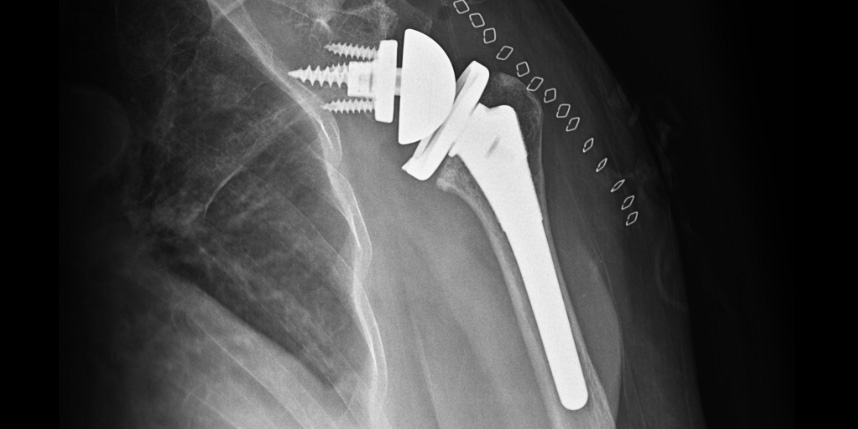

인공관절 치환술

삼하게 망가져 거의 기능이 없는 관절을 제거한 후 특수하게 제작된 인공관절을 삽입하는 수술

비수술 치료에도 호전이 없는 경도의 관절염에서 시행합니다.